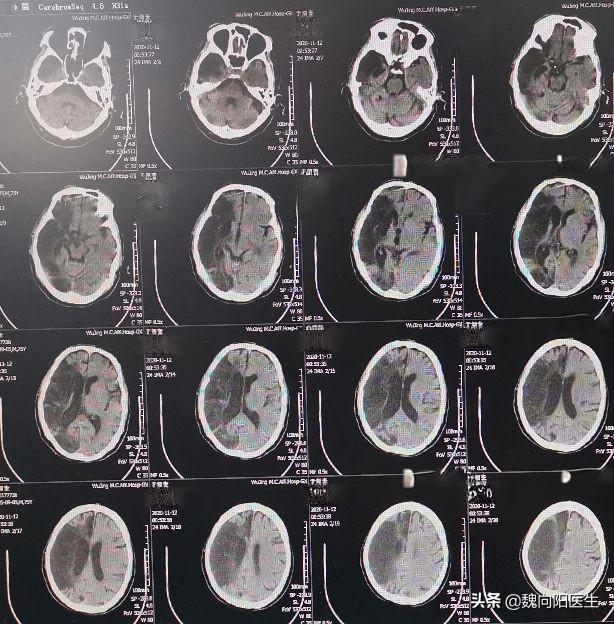

脑梗死非得要做核磁才能发现吗?做CT行不行?

脑梗死的诊断并不一定需要核磁共振(MRI),在某些情况下,计算机断层扫描(CT)也是可行的。然而,MRI在早期诊断脑梗死方面具有明显优势。

一项研究比较了CT和MRI在脑梗死早期诊断中的价值。结果显示,CT检查诊断出8例脑梗死,准确率为16.0%;而MRI诊断出48例,准确率高达96.0%。这表明MRI在早期诊断脑梗死方面明显优于CT。